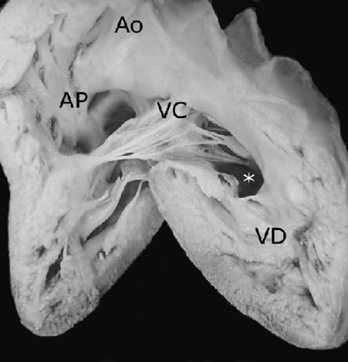

Se describieron morfológicamente 2 corazones univentriculares con doble entrada y anomalía de Ebstein de la válvula auriculoventricular común que forman parte de la colección patológica del Instituto Nacional de Cardiología Ignacio Chávez. Se utilizó como método descriptivo morfológico el sistema secuencial segmentario empleado en el diagnóstico de las cardiopatías congénitas4. Se determinaron el situs auricular, los tipos y modos de conexión auriculoventricular y ventriculoarterial, los defectos septales y las anomalías asociadas; en especial se describieron las características anatómicas de la válvula auriculoventricular. Se determinó el grado de adosamiento y desplazamiento valvares con el método de Becker et al.1. Para establecer las porciones auricularizada y ventricular funcional; se compara la anomalía de Ebstein de la válvula tricúspide con la de estos corazones univentriculares para resaltar sus rasgos comunes y sus diferencias básicas

Los 2 corazones formaron parte de un situs solitus auricular, ambos con doble entrada a ventrículo único a través de una válvula auriculoventricular común cuyas valvas estuvieron adosadas a la pared ventricular; las grandes arterias normalmente relacionadas emergieron del ventrículo único con estenosis pulmonar infundibular y valvular (Fig. 5); el adosamiento y desplazamiento valvares cubrieron toda la porción de entrada y la zona trabecular posterior hasta la región apical con una gran auricularización del ventrículo único; estuvieron ausentes las cuerdas tendinosas y los músculos papilares (Fig. 6); la porción funcional efectiva del ventrículo se redujo a la zona trabecular anterior y a la región infundibular (Fig. 5). En el segundo corazón las grandes arterias estuvieron también normalmente relacionadas pero con dilatación y ambas emergieron del ventrículo único (Fig. 7). El adosamiento y desplazamiento valvares estuvieron reducidos a la porción proximal de la válvula por lo que la auricularización fue menor y mayor la porción funcional del ventrículo único (Fig. 8). Ambos corazones tuvieron un tabique interauricular pequeño con foramen primum (Tabla 1).